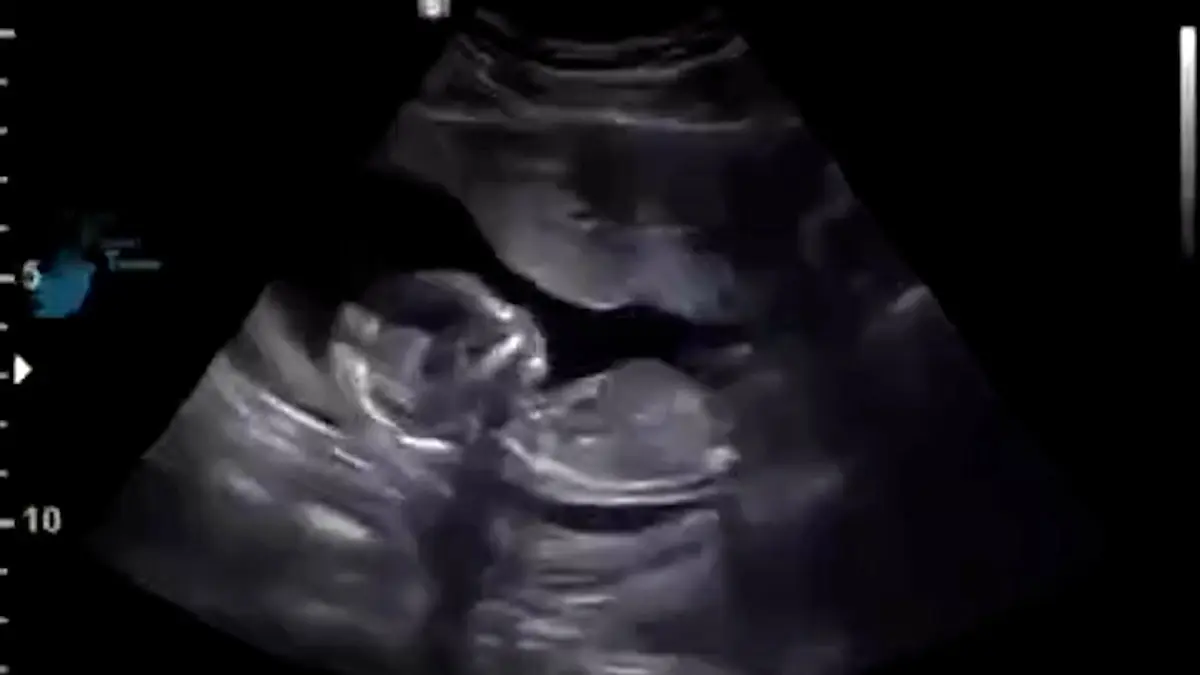

فیلم پربازدید سکسکه جنین 12 هفته ای قبل از تولد .../ مبهوت میشید

رکنا: فیلم سنوگرافی جنین 12 هفته ای را میبیند که در شکم مادرش در حال سکسکه کردن است.

به گزارش رکنا،در این فیلم جنین ۱۲ هفته ای را میبینید که به دلیل دریافت بیش از حد مایع آمنیوتیک در شکم مادر سکسکه می کند.